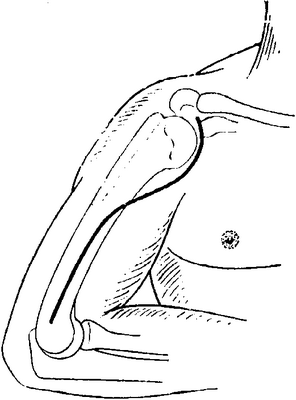

После консолидации перелома через 71 день произведен демонтаж аппарата (рис. 5). Рисунок 5. Рентгенограммы больной П. после остеосинтеза левой плечевой кости спице-стержневым аппаратом. Движения в левом локтевом суставе после демонтажа аппарата от 0 до 128° (рис. 6). Рисунок 6. Внешний вид больной П. после демонтажа аппарата (объем движений в левом локтевом суставе от 0 до 128°).